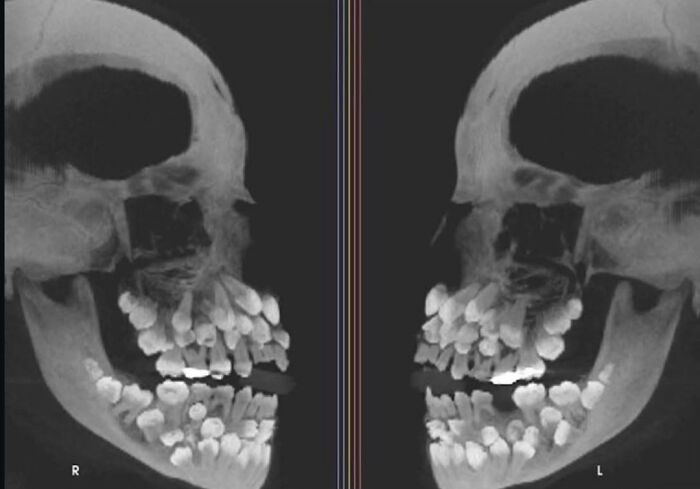

To wyglądają wszystkie nerwy związane z twoimi zębami

RTG pacjenta z hiperodoncją (więcej zębów niż zwykle). Dorosłe osoby mają zwykle 32 zęby — ta osoba miała 81